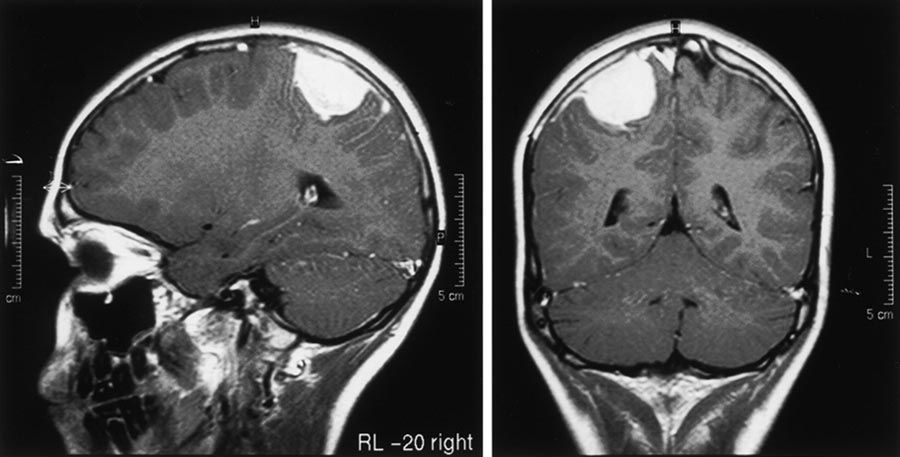

1. Estudios radiológicos:

1. Muestran efecto de masa, así como cambios en el encéfalo adyacente al tumor, como edema. Astrocitomas de alto grado - - - > vasos anómalos que están agujereados y por ello muestran refuerzo con contraste en los estudios de imagen.